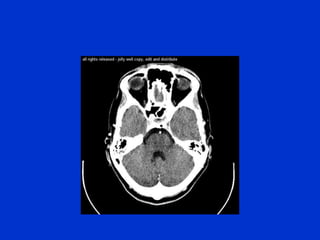

The document provides an overview of normal brain anatomy including key structures like the central sulcus, lateral sulcus, white matter tracts, brain stem, ventricular system, and basal cisterns. It was authored by Dr. Maliha Fansur, Assistant Professor at SIMS/SHL, who appears to have expertise in neuroanatomy.